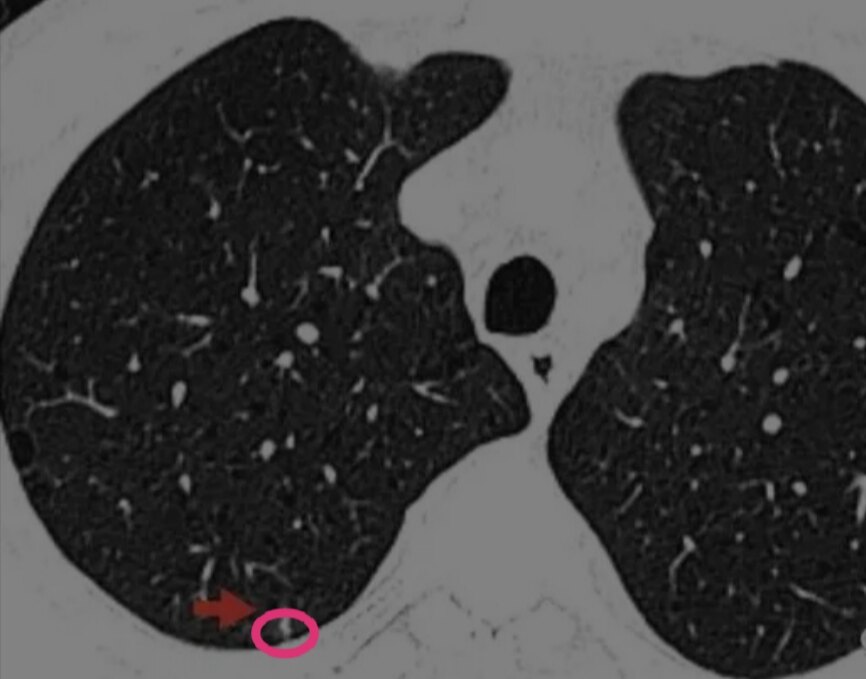

右下肺后段肺部微小实性结节

此为实性结节,5mm,没有毛刺征、胸膜凹陷征及血管弯曲等任何肿瘤的特征性表现。单凭这个CT,任何一个医生或者人工智能AI,都可能会认为这个结节良性可能大,无法确认这个结节是肺癌。

这个时候,就需要通过患者的临床特点和连续动态胸部CT检查结果:肺部结节发生发展趋势来判断肺结节良恶性了。

首先,男性、吸烟、肺气肿背景,是肺实性结节为恶性的危险因素,也是肺磨玻璃结节生长的危险因素。因此这个患者的肺结节需要重视。